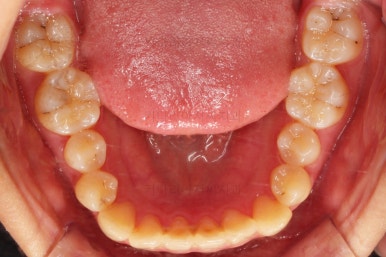

충치가 곳곳에 보이는데요.

성인들은 충치가 멈춰있는 정지우식일 가능성도 있으며 크기가 현재 크지 않고 향후 변화되지 않는다면 그대로 두기도 합니다.

이번 환자분도 교정치료에 방해되는 부분이나 급해보이는 추료만 우선 진행하고 교정 중에 충치가 커지는지 증상이 생기는지 관찰해 보기로 했습니다.

덧니가 완전히 개선디ㅗ었고 필요한 충치치료도 부분적으로 진행했고요.

중앙선이나 교합도 양호하게 마무리 했습니다.